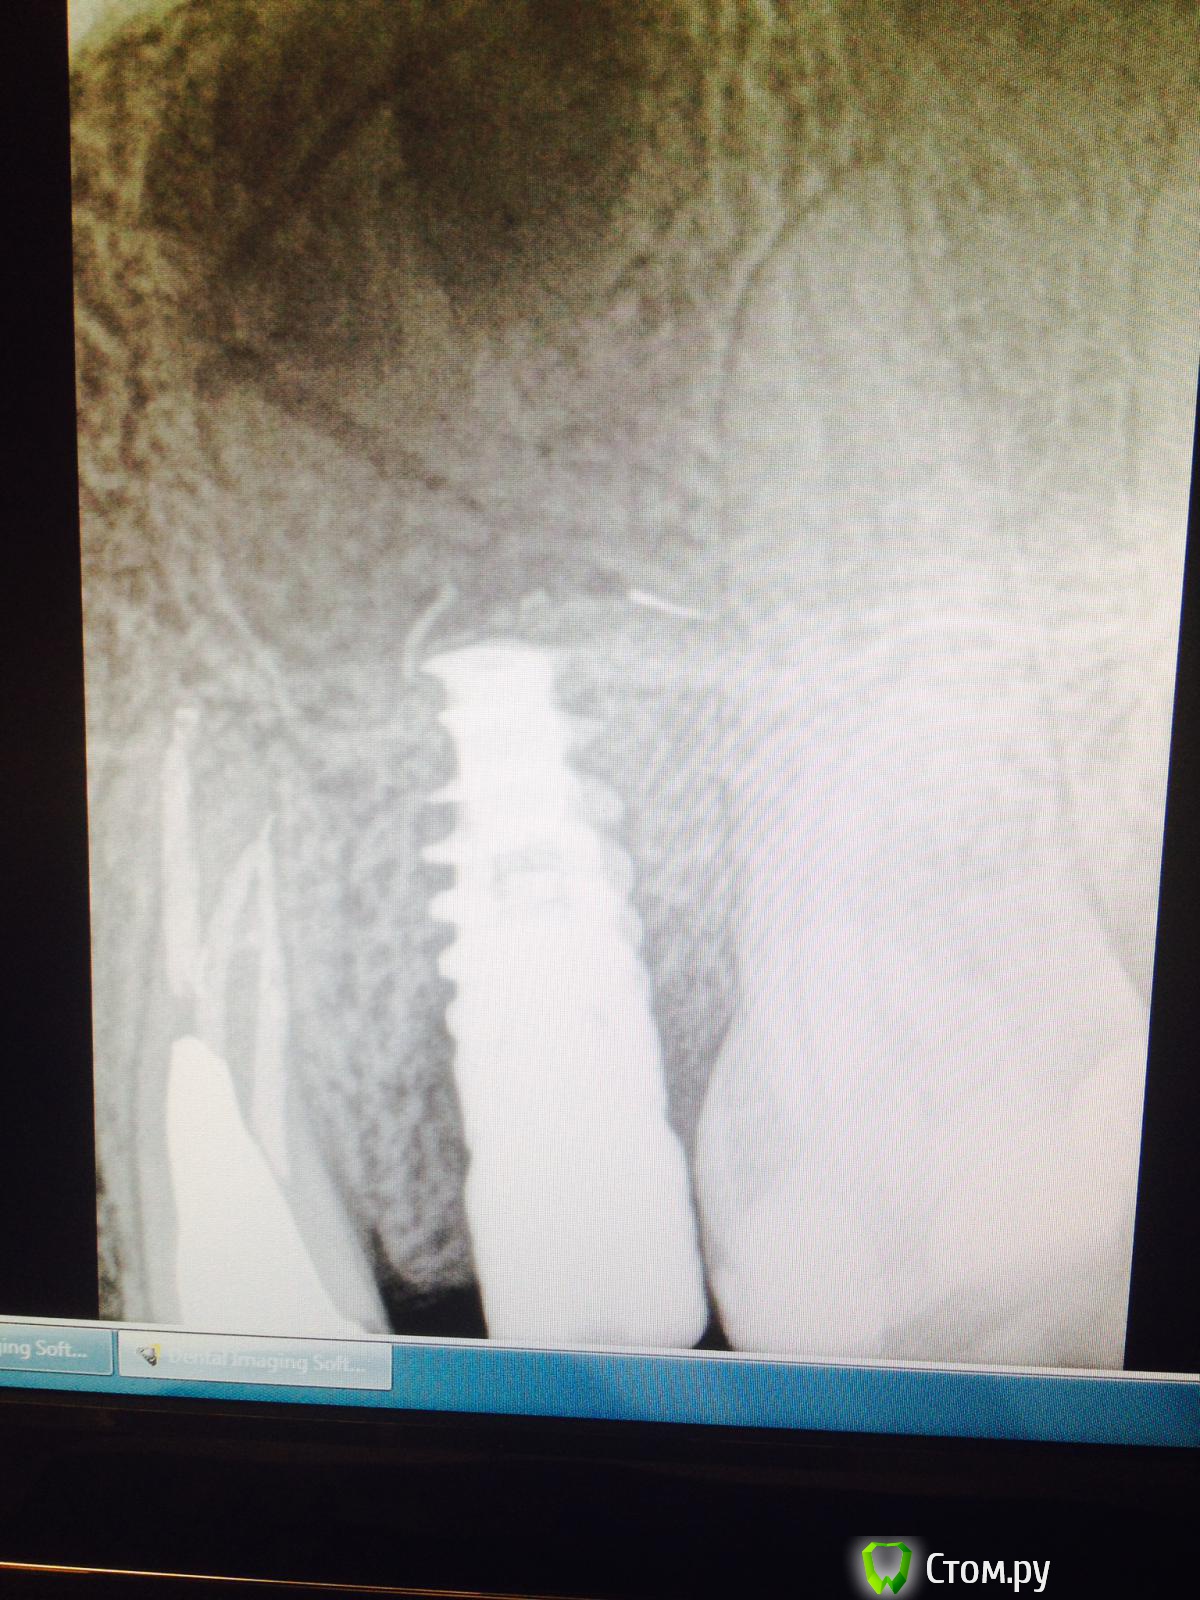

Тимур86 Опубликовано 17 июня, 2014 Поделиться Опубликовано 17 июня, 2014 Господа!пациентке около 4 месяцев тому назад был установлен имплантат в области 25!альфа спи 4.2/10,кт нету под рукой,но проблем с костью небыло вообще (10/10мм по-моему)!в общем имплантация как по учебнику!торк 30-35,сверлил не больше 1000 об.все зажило норм!пришла на фдм-поставили!после установки фдм жаловалась на дикие боли в области импланта!как при пульпите!всю голову сломали,26 по пульпиту пролечили(там пломба глубокая была)в общем вчера,недели через 3 после установки фдм,ортопед вытащил пальцами имплантат...вопросы:1-по какой причине это могло случиться?если дезинтеграция-то почему при установке фдм не вылетел?торк был 30!2-если предположить что боли все-таки были связаны с имплантатом,то что же там так могло болеть на протяжении почти 2- недель? Ссылка на комментарий

КДБ Опубликовано 17 июня, 2014 Поделиться Опубликовано 17 июня, 2014 рентгенологически и до лечения 6го были изменения в области имплантата 1 Ссылка на комментарий

КДБ Опубликовано 17 июня, 2014 Поделиться Опубликовано 17 июня, 2014 у меня часто какие-то изменения рентгенологически в первые месяцы!связывал это с ремоделировкой кости...явно носит воспалительный характер и 1 снимок и еще выраженней 3й Ссылка на комментарий

GAN Опубликовано 17 июня, 2014 Поделиться Опубликовано 17 июня, 2014 На момент установки ФДМ имплант мог не быть остеоинтегрирован, а якобы стабильность ему придала агрессивная резьба, ФДМ при закручивании провернул его...вот и ушёл винт. Мне SPI принципиально не нравятся как раз из за агрессивной резьбы. А на момент установки могли и фрезы быть тупыми-перегрел кость, когда меняли в последний раз? 5 Ссылка на комментарий

Тимур86 Опубликовано 17 июня, 2014 Автор Поделиться Опубликовано 17 июня, 2014 На момент установки ФДМ имплант мог не быть остеоинтегрирован, а якобы стабильность ему придала агрессивная резьба, ФДМ при закручивании провернул его...вот и ушёл винт. Мне SPI принципиально не нравятся как раз из за агрессивной резьбы. А на момент установки могли и фрезы быть тупыми-перегрел кость, когда меняли в последний раз?тоже об этом думал...но 4 месяца!торк 30...с чего бы не произойти остеоинтеграции?и фдм-ку на 30 закручивал,все ровно было... Ссылка на комментарий